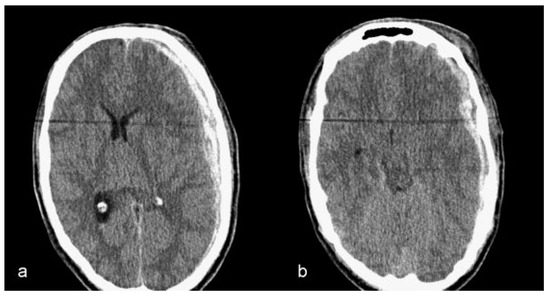

De Water, V.R.; dos Santos Rubio, E.J.; Schouten, J.W.; Koudstaal, M.J. Deformation of a Titanium Calvarial Implant following Trauma: A Case Report. Craniomaxillofac. Trauma Reconstr. 2016, 9, 158-161. https://doi.org/10.1055/s-0035-1567810